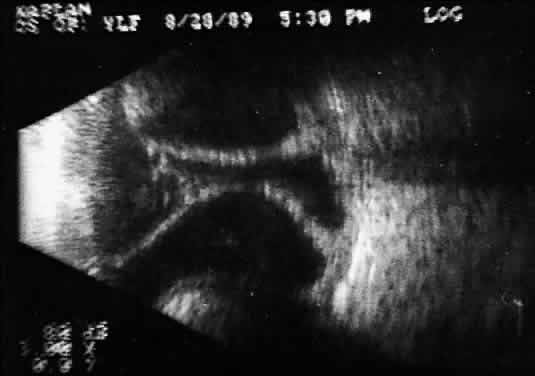

Fig. 5. Contact B-scans. A. Heavy formed vitreous hemorrhage obscuring choroidal mass. B. Voluntary movement of the globe causes the formed vitreous to shift, permitting easy detection of the ocular wall mass.